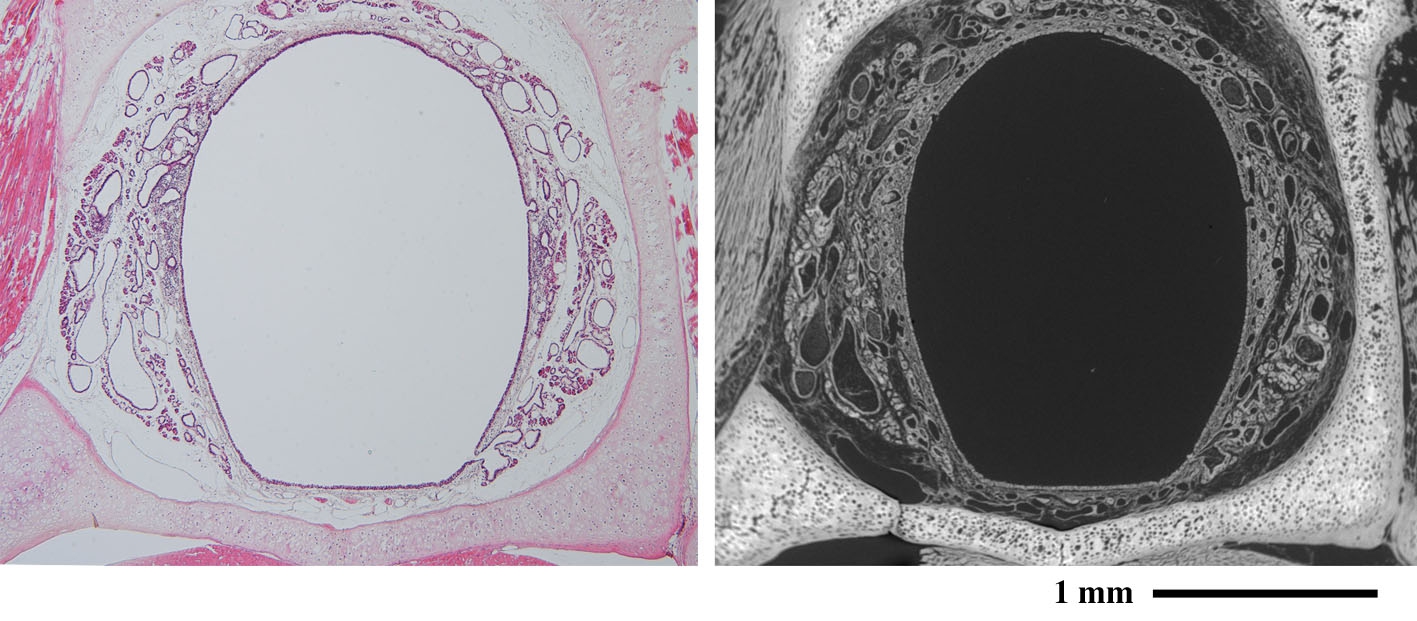

喉頭(ラット) Larynx ( rat )

(左:パラフィン切片のヘマトキシリン・エオジン染色光顕像/右:低真空SEM像)

中央の大きなトンネルが気管です。